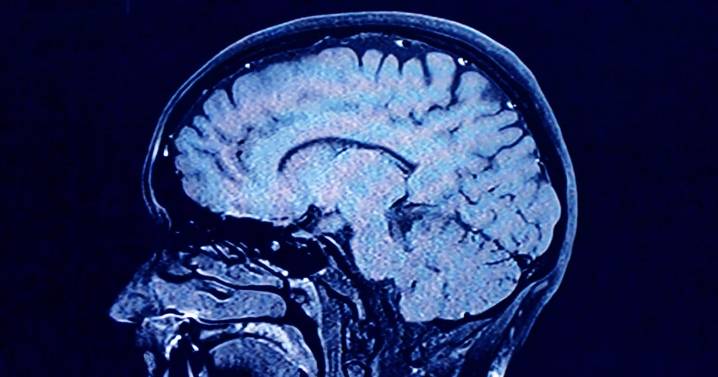

As we age, the human brain rewires itself.

The process happens in distinct phases, or “epochs,” according to new research, as the structure of our neural networks changes and our brains reconfigure how we think and process information.

For the first time, scientists say they’ve identified four distinct turning points between those phases in an average brain: at ages 9, 32, 66 and 83. During each epoch between those years, our brains show markedly different characteristics in brain architecture, they say.

The findings, published Tuesday in the journal Nature Communications , suggest that human cognition does not simply increase with age until a peak, then decline. In fact, the phase from ages 9 to 32 is the only time in life when our neural networks are becoming increasingly efficient,